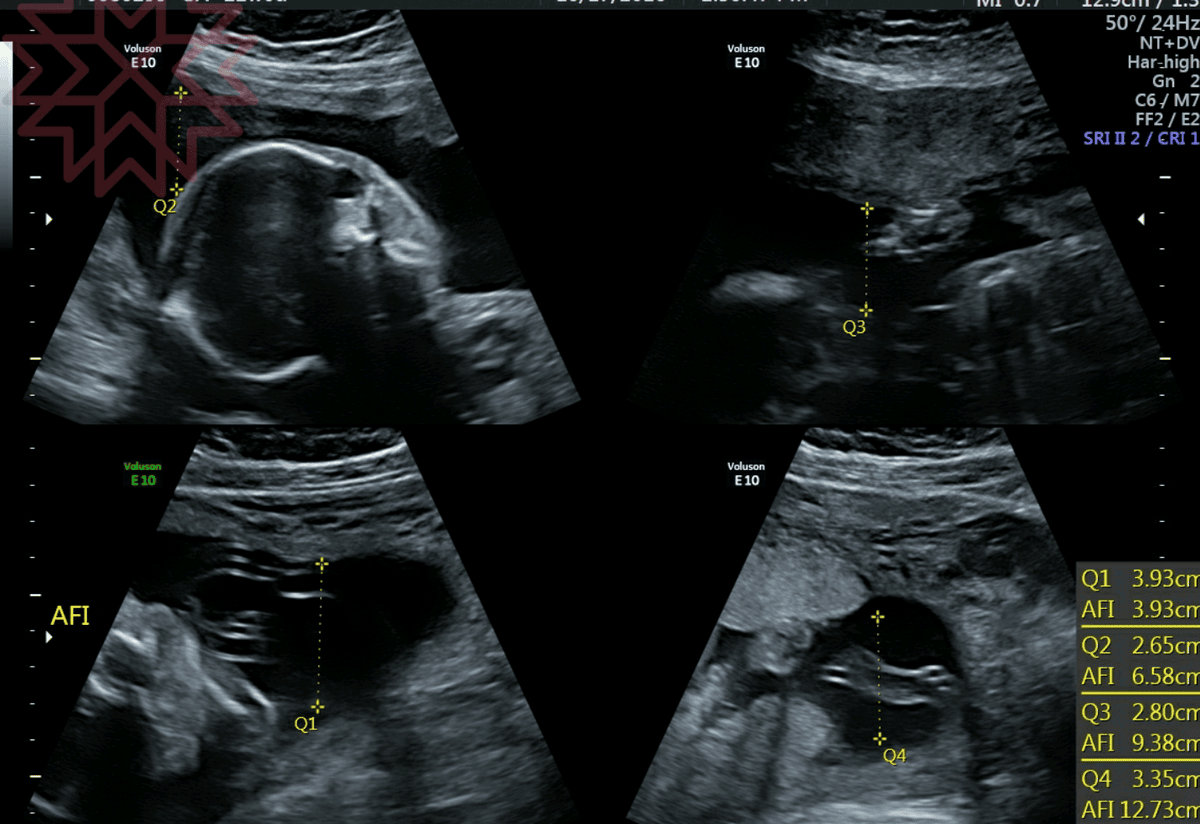

禾馨的超音波算有名的清楚

高層次會先由技師照一遍,然後再由醫生照一遍

全部的報告就是下面兩張的紙本

還有此次超音波影像全部的彩色列印

是看了報告以後才知道的